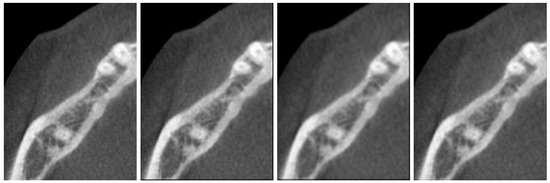

3. Numerical Results